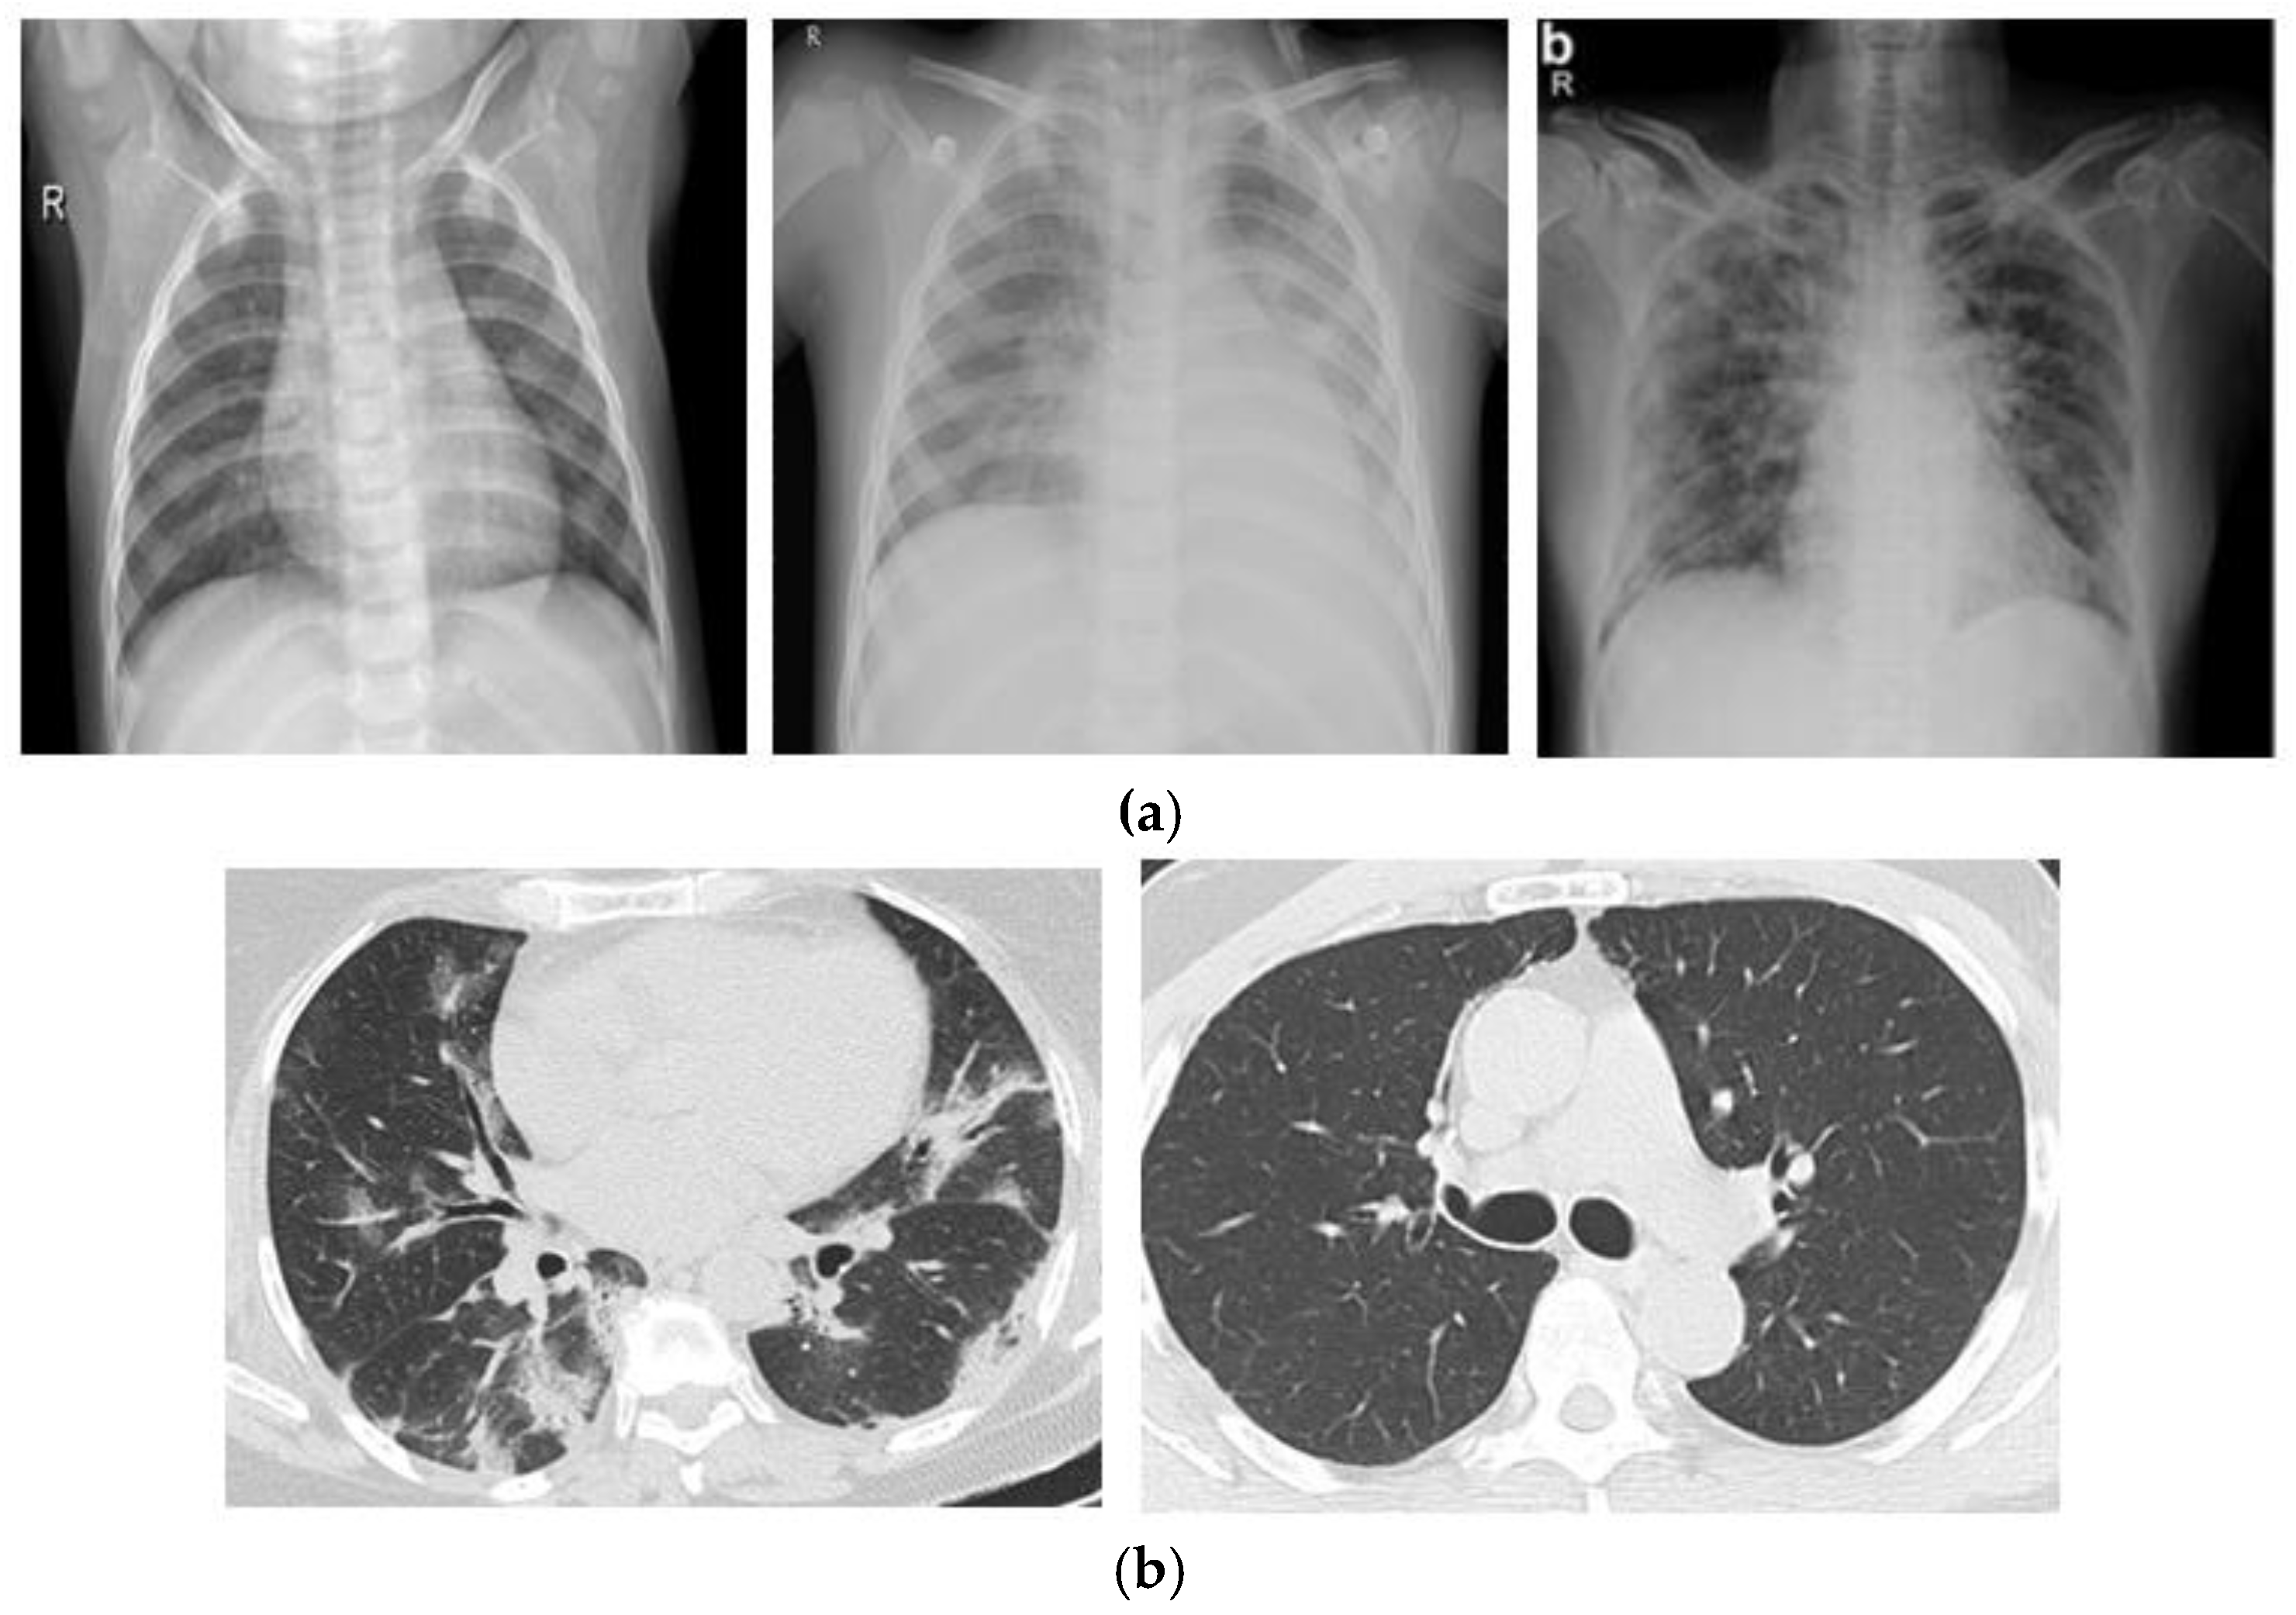

3.1. Dataset